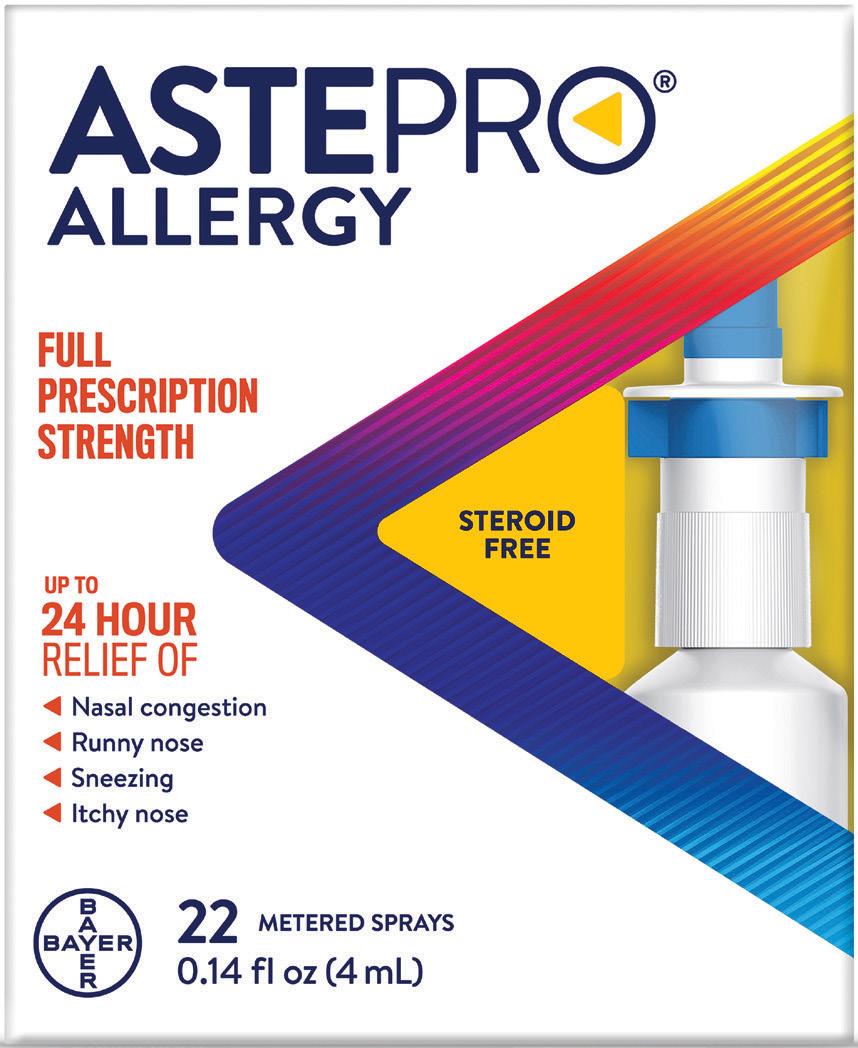

144 Cool New Products

164 Category Close-Up

Consumers sought the comfort of confections during the pandemic, and the trend continues.

176 By the Numbers

The per-store, per-month gross profit for the candy category in 2021.